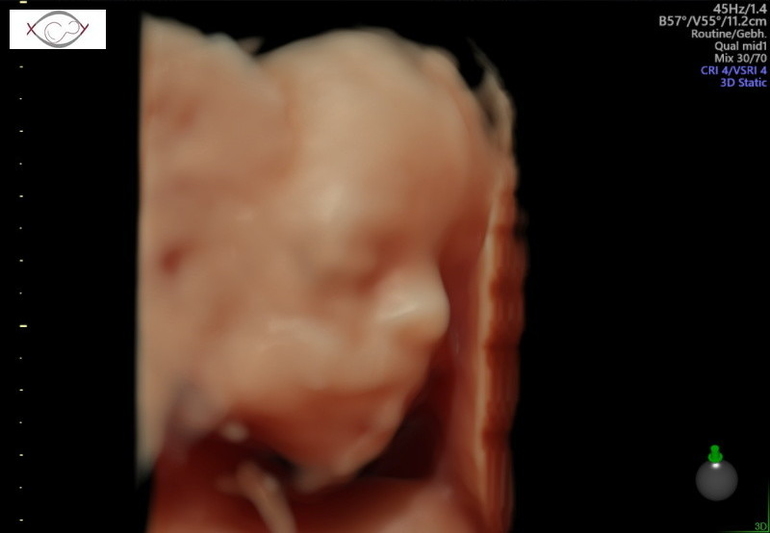

Теперь я особо ничего уже не боюсь👍 2,5 недели назад писала пост о не полном предлежании плаценты, она за это время поднялась и уже 2,5 см от зева🤗Ура, ура, ура🥳🥳🥳 Особо беременной себя до сих пор не чувствую, в том плане, что ни отёков, ни какого то дискомфорта пока не ощущаю, но жду, готовлюсь морально🤪. Для папы нашего сделали фото писюна, чтобы уж точно он уже был уверен, что мальчик😅🤣🤣🤣 Пяточку, которой малой мне пиночки отвешивает и личико попытались сфоткать, но скромняшка всё ручками закрывался.

Поздравляю! Как хорошо, что плацента поднялась 🙂. Теперь можно наслаждаться беременностью. Фотографии супер получились😍.